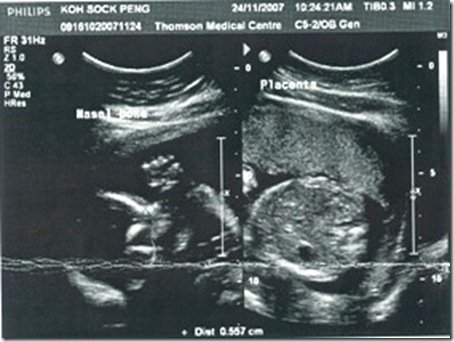

24/Nov/2007